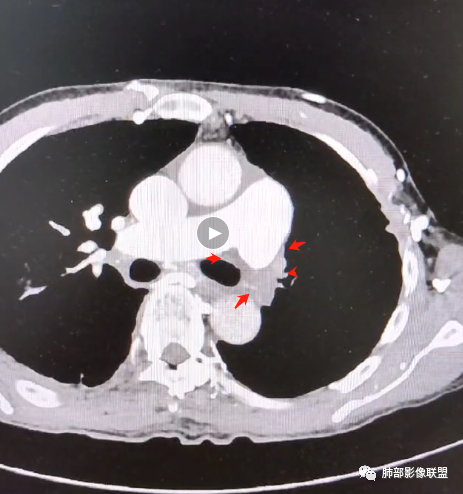

6.心脏影增大,右房室增大为主。(增强:左心房及肺静脉入口见充盈缺损)

7.肺动脉主干扩张,左侧肺动脉主干见混杂密度影,上下肺动脉似不能连续追踪。

(增强:左肺动脉充盈缺损、闭塞)

5.影像左肺动脉栓塞、闭塞——上下肺动脉以远相对纤细——左肺动脉“断供”,且存在支气管动脉扩张可能。